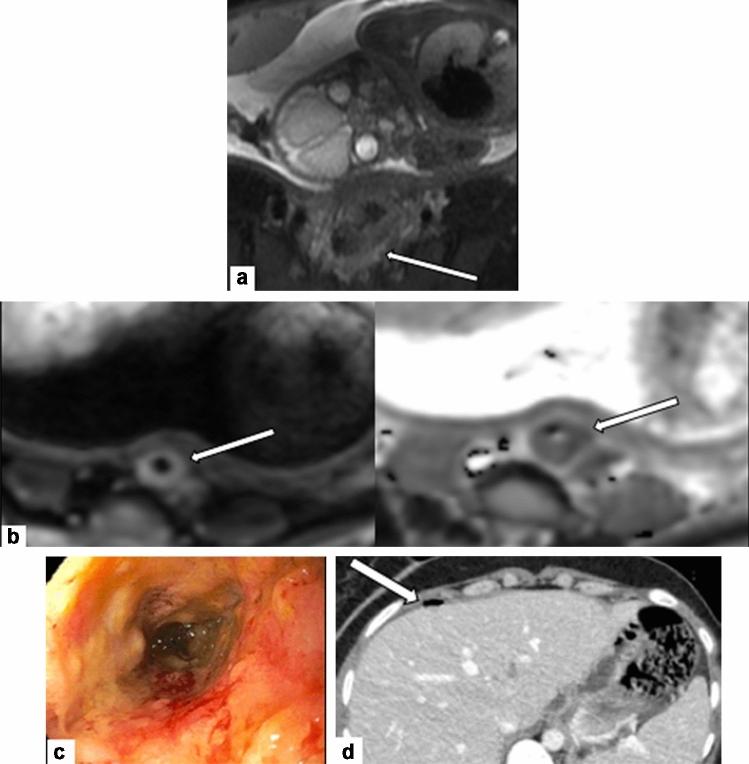

Pregnancy-associated cancer (PAC) occurs in approximately 1 in 1000 pregnancies, and the incidence is expected to rise due to delayed childbearing (Silverstein et al. in JCO Oncol Pract 16:545-557, 2020; Woitek et al. in ESMO Open 1:e000017, 2016). Diagnosis and management of PACs are challenging and diagnosis is often delayed as symptoms may overlap with physiologic changes of pregnancy (Jha et al. in RadioGraphics 42:220005, 2022). These patients are best cared for by a multidisciplinary healthcare team composed of experts (Silverstein et al. in JCO Oncol Pract 16:545-557, 2020). Management of these patients must balance optimal maternal care with potentially harmful fetal effects. This involves honest, forthright, and sometimes difficult discussions between the care team and the patient throughout the entirety of care. Radiologists play a significant role in timely cancer diagnosis, staging and follow-up during and after pregnancy, accurate determination of gestational age, and in assessing fetal growth and well-being throughout pregnancy.

妊娠相关癌症(PAC)在大约每 1000 次妊娠中发生 1 次,由于生育年龄推迟,其发病率预计将会上升(Silverstein 等人,在 JCO Oncol Pract 16:545-557,2020;Woitek 等人,在 ESMO Open 1:e000017,2016)。PAC 的诊断和管理具有挑战性,且诊断往往被延误,因为症状可能与妊娠的生理变化相重叠(Jha 等人,在 RadioGraphics 42:220005,2022)。这些患者最好由多学科医疗团队的专家进行治疗(Silverstein 等人,在 JCO Oncol Pract 16:545-557,2020)。这些患者的管理必须在最佳的母婴护理与胎儿潜在有害影响之间取得平衡。这需要护理团队与患者在整个护理过程中进行坦诚、直率,有时甚至是困难的讨论。放射科医生在妊娠期间和妊娠后及时进行癌症诊断、分期和随访、准确确定胎龄以及评估胎儿生长和健康方面发挥着重要作用。